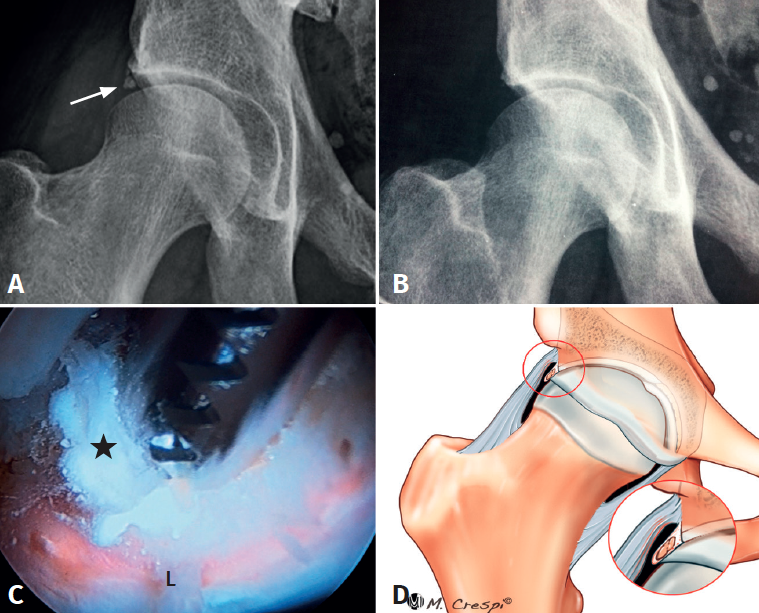

- Características y morfología radiográfica: pequeño núcleo radiodenso adyacente al borde lateral del acetábulo con mayor opacidad en comparación con el hueso trabecular vecino, con bordes esponjosos y mal definidos, sin evidencia de hueso trabecular o márgenes corticales y con un tamaño significativamente menor que el os acetabuli o tipo A2 (Figura 1).

- Tratamiento: estas lesiones son fácilmente localizadas y tratadas por vía artroscópica. Mediante el uso combinado de palpador, sinoviotomo y radiofrecuencia se realiza su extirpación. Debido a sus características amorfas, no son susceptibles de extraer mediante una pinza de tipo grasper. En nuestra experiencia, generalmente tras su evacuación suele quedar suficiente tejido labral para realizar una reparación con anclajes. En caso de morfología de choque, se debe realizar acetabuloplastia en casos de deformidad de tipo pincer y osteoplastia femoral en caso de deformidad de tipo cam.

- Características y morfología radiográfica: gran tamaño, forma redondeada u ovoide, situadas ligeramente a distancia del acetábulo y separadas en relación con el techo acetabular por una línea radiolúcida oblicua u horizontal (Figura 2).

- Tratamiento: este tipo de calcificación se puede reducir o extirpar mediante fresa o en algunos casos extraer con una pinza de tipo grasper como un cuerpo libre tras diseccionarla y separarla cuidadosamente con radiofrecuencia, bisturí y sinoviotomo. A continuación, se debe proceder a la reparación labral del labrum subyacente y, en caso de daño importante o funcionalidad escasa tras la extirpación, complementarlo con una reconstrucción o una aumentación labral.

- Características y morfología radiográfica: tamaño grande y línea de fractura perpendicular o vertical en relación con el techo acetabular (Figura 3).

- Tratamiento: dependiendo de la cobertura que quede tras la extirpación, se decidirá si enuclear el fragmento o fijarlo. La planificación preoperatoria es por tanto crucial para garantizar que la escisión de la fractura/fragmento no dé como resultado una cobertura insuficiente o una inestabilidad iatrogénica. La medición del ángulo centro borde lateral y anterior al nivel de la extirpación planificada puede dar una indicación de una cobertura insuficiente resultante si el fragmento contribuye a la estabilidad de la cadera. En estos casos, debe considerarse la fijación quirúrgica mediante fijación con tornillo canulado asistida por artroscopia a través de la unión fibrocartilaginosa(4). En casos de fragmentos grandes que contribuyan simultáneamente al pinzamiento y la estabilidad, se puede realizar resección parcial y fijación del remanente. La utilización de una sutura sobre el tornillo de fijación ayudará a realizar la fijación labral sin tener que usar un arpón o anclaje(4)(Figura 4).